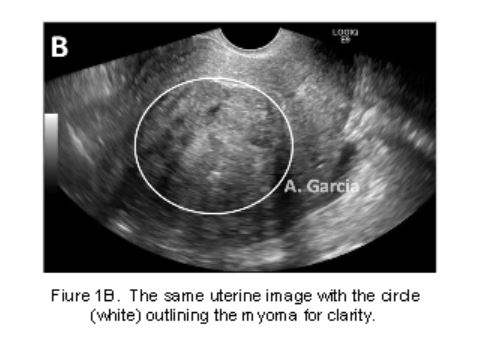

A 2-dimensional transvaginal ultrasound (2DTVUS) is generally the first-line diagnostic procedure for evaluating AUB for most women.(Figura 1) It is a safe and cost-effective tool which is fully utilizable in the office. Initial 2DTVUS findings of any endometrial abnormality, presence of fibroids or suspicion of adenomyosis warrants evaluation of the cavity with hysteroscopy.

Power Doppler is more sensitive than color Doppler for the detection of blood flow but provides no information about the direction of flow. When added to gray scale TVUS, circular vessel flow pattern correlates with a high level of specificity for the diagnosis of submucous myomas compared to HS (sensitivity 72.2%, specificity 100%, PPV 100% and NPV of 88.9%). There are differences, however, in diagnostic accuracy of intracavitary pathology between 2DTVUS, saline infusion sonography (SIS) and hysteroscopy. In a large systematic review of studies comparing these three imaging techniques, both SIS and HS identify intrauterine pathology better than 2DTVUS.